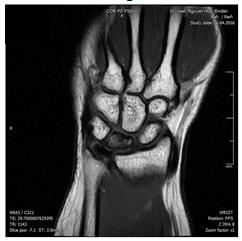

Da fiel mir mein Cousin ein, der praktischerweise Handchirurg ist und ich fragte ihn am Telefon, was ich tun solle. Er riet zu einem Röntgenbild und MRT mit Kontrastmittel, wenn 10 Tage entzündungshemmende Schmerzmittel nichts helfen, stimme was nicht! Scheinbar mein Glück, wenn ich höre, wie lange andere bis zur sinnvollen Diagnostik brauchten. Das MRT wurde am 24.4.2016 durchgeführt. Der Radiologe holte mich an seinen Schreibtisch, zeigte mir die Bilder (alle anderen Knochen weiß und einer schwarz bzw. andersrum) und nannte mir die Diagnose Lunatummalazie.

Eine MRT-Kontrolle im Februar 2017 zeigte eine Progredienz, beginnende Fragmentation und Formveränderung des Lunatum, eine neue skapholunäre Dissoziation und zunehmende Gelenkspaltverschmälerung radiokarpal. Ich hatte auch immer noch Schmerzen (genau an gleicher Stelle wie vor der OP aber nicht ganz so schlimm) und die Beweglichkeit war immer noch schlechter als vor der 1. OP.